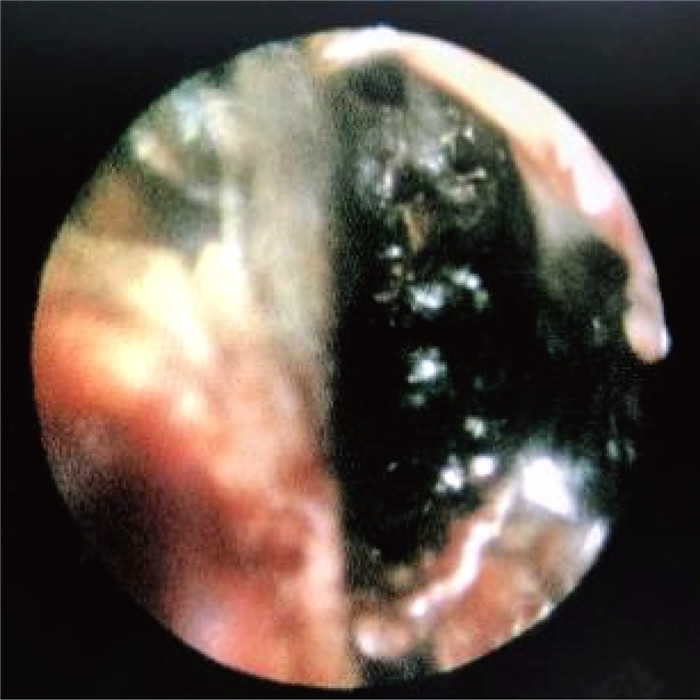

1.3 病情变化及预后患儿入院即存在中性粒细胞缺乏伴发热,感染控制后予以诱导缓解治疗(VDLD):长春新碱(vincristine)+柔红霉素(daunorubicin)+培门冬(pegaspargase)+地塞米松(dexamethasone)。患儿第13天再次出现发热,多次调整抗感染方案,先后曾给予美洛培南、万古霉素、伏立康唑、卡泊芬净、两性霉素B等抗感染治疗,体温控制欠佳,无热期1~2天,C反应蛋白(C-reactive protein,CRP)最高升至216 mg/L,降钙素原为2.27 ng/mL。期间多次完善胸部计算机断层扫描(computed tomography,CT)、腹部超声,均未提示明确异常。血培养、骨髓培养、脑脊液培养提示无菌生长,1,3-β-D葡聚糖抗原检测及半乳甘露聚糖抗原检测试验(G/GM试验)结果为阴性。VDLD诱导缓解治疗第19天患儿诉上门齿疼痛,经口腔科会诊及颌面部超声检查未提示明显异常,VDLD治疗第30天患儿出现左侧眼睑肿胀,伴有少量分泌物,给予妥布霉素滴眼液滴眼。VDLD诱导缓解治疗完成后第2天,患儿出现右侧鼻出血,左侧鼻腔流涕,且伴有喉中痰鸣,完善痰培养,并于耳鼻喉科行鼻腔镜检查,镜下双侧鼻腔可见血痂、干酪样物质,右侧中鼻甲、鼻中隔黏膜糜烂、吸收、缺如,骨质裸露、部分缺损,中鼻道霉菌团块,后鼻孔见坏死性干痂(见图 1),鼻腔分泌物行涂片检查: 找到真菌无隔菌丝(见图 2),分泌物及痰培养提示霉菌生长(见图 3)。急查头颅CT,见左侧颞叶低密度。行头颅磁共振成像(magnetic resonance imaging,MRI)平扫+增强,提示:左侧颞叶多发异常信号,右侧基底节区及左侧颞叶多发弥散受限灶,右侧颞叶病变内强化灶;蝶窦、左侧鼻腔、左侧上额窦、筛窦信号增高,结构欠清,前额部部分软脑膜明显强化,结合患者的病史,考虑真菌感染可能性大(见图 4)。患儿发热期间曾给予两性霉素B静滴,终因肾功能损害及低钾血症而暂停应用。患儿鼻眶脑型毛霉菌病诊断明确后立即给予两性霉素B脂质体(锋克松)静点,初始剂量0.5 mg/kg/d,逐渐增至2.5 mg/kg/d维持,同时予泊沙康唑90 mg/次,一日4次口服;期间给予两性霉素B雾化及鞘内注射,鞘内注射初始剂量为0.1 mg,逐渐增加至最大1 mg,每周2~3次,出院前共鞘注7次,两性霉素B总量为3.55 mg,期间因患儿头痛、血压高而减少鞘注剂量。患儿在接受两性霉素B脂质体抗真菌治疗期间出现肾功能损害及低血钾,予以调整两性霉素B脂质体剂量及静脉补钾治疗。应用两性霉素B脂质体抗真菌治疗后患儿热峰降低,C反应蛋白降至15 mg/L,左侧眼睑肿胀减轻,精神状态较之前明显好转,但患儿出现左侧上睑下垂,左眼球活动障碍,双侧瞳孔不等大,视物不清,复查头颅磁共振增强扫描,提示:脑内多发异常信号,右侧基底节区病变略缩小,余病变较前增大(见图 5), 建议家属待患儿血象恢复后手术切除感染灶,家属要求出院,院外继续口服泊沙康唑,未行手术及化疗,半年后死于白血病复发。

| 图 3 分泌物培养可见霉菌 Fig. 3 Visible mold in secretion culture |